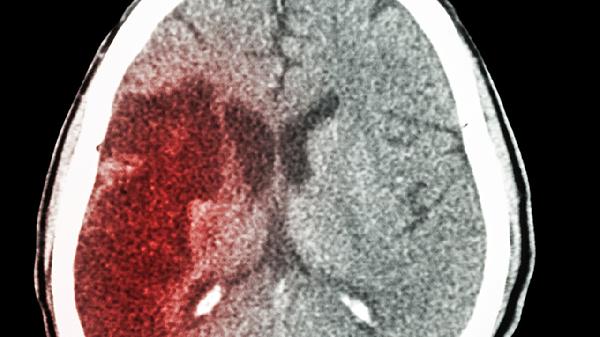

脑得生片主要用于治疗脑动脉硬化、脑供血不足等疾病引起的头晕、头痛等症状。使用时应遵医嘱,避免自行用药。服药期间注意饮食清淡,避免油腻、辛辣食物,保持良好的作息习惯有助于药效发挥。如出现不适症状应及时就医。